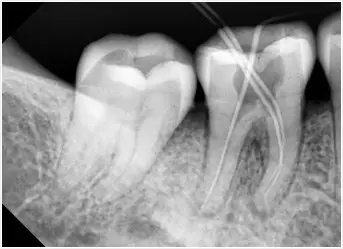

根管治療過程比較複雜,通常可能需要3次甚至更多的時間,而且術前術中術後都需要拍X片查看根管治療的情況,此外,在根管治療時,通常需要進行局部麻醉下操作。

拍牙片確定根管長度